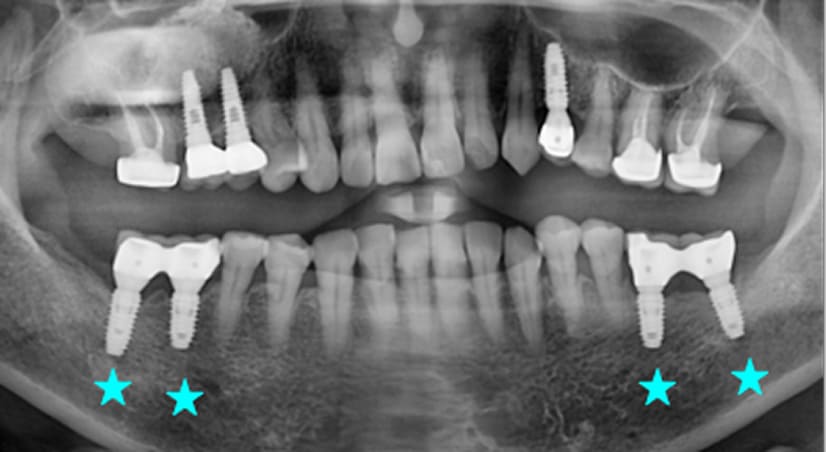

13+ 年

-

种植体植入:2012 年 9 月 -

最终修复体:2013 年 1 月 -

随访:13 年(2025 年 1 月)

种植体植入 2012年10月 -

最终修复体 2013年1月 -

随访:13年 2025年3月

9年以上

随访:2年 2014年7月 -

随访:9年 2021年9月